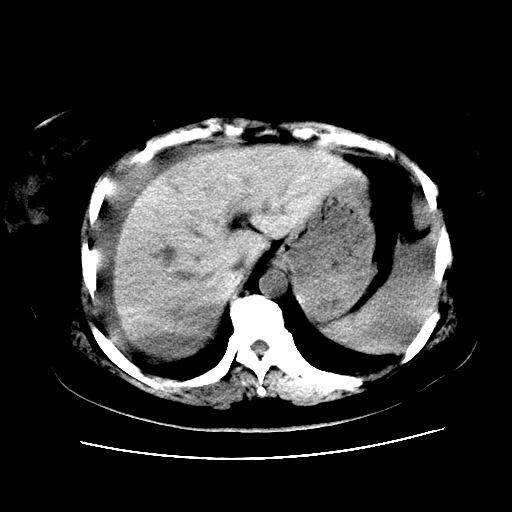

f,45y.怀孕4月晕倒,b超提示死胎,有手术结果,请展开讨论后明天告诉。

膈下-肠间隙内见气体密度影,子宫轮廓显示不清,宫腔-腹腔积液,首选考虑---子宫破裂出血。

1)宫腔妊娠。2)子宫破裂出血,腹腔及盆腔积血。

怀孕4个月晕倒,病史就这么简单?有没有腹痛呢?腹腔内有没有气体?窗宽太窄了脂肪组织与气体已不好分。如果有气体,那就是空腔脏器穿孔,如胃肠穿孔。如没有气体,就考虑子宫破裂或宫外孕破裂。正常怀孕子宫破裂很少见,有可能是宫外孕。极有可能是残角子宫怀孕破裂。腹腔怀孕破裂也有可能。

感谢同行们的高见。手术结果:子宫破裂出血。

我们的诊断是:腹、盆腔积液(考虑腹盆腔脏器破裂出血);宫腔妊娠。让人纳闷的是当时我们没有经验,现在回头看看分析:4月宫腔妊娠:1、洋膜囊不可能紧贴胎体这么小;2仔细看看子宫后壁肌层模糊不清;3腹、盆腔液体来源原因?4、45岁高龄妊娠有晕倒。由此可大胆诊断:宫腔妊娠子宫破裂出血。